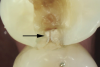

Fig 1. Decalcification in enamel along a crack line (arrow) and caries at the dentin-enamel junction of a mandibular left first molar (disto-occlusal view).

Figure 1

The detrimental effects of vertical cracks on the dentition and surrounding tissues stem mostly from bacterial invasion into the microscopic space of the crack, as well as physical irritation and liquid microleakage, even though the separation of the segments may not be clinically visible.3,5-7As bacteria penetrate cracks, they invade underlying structures, such as the coronal dentin, pulp, root structure, and periodontal tissues, leading to varying degrees of pathologies. Enamel cracks have been found to provide caries-producing bacteria access to the dentin-enamel junction, leading to caries inside the tooth without any externally visible evidence (Figure 1).5 Dentin cracks are pathways of bacteria to the dentinal tubules and pulp, leading to various pulpal pathologies, including reversible and irreversible pulpitis and pulp necrosis.6,8